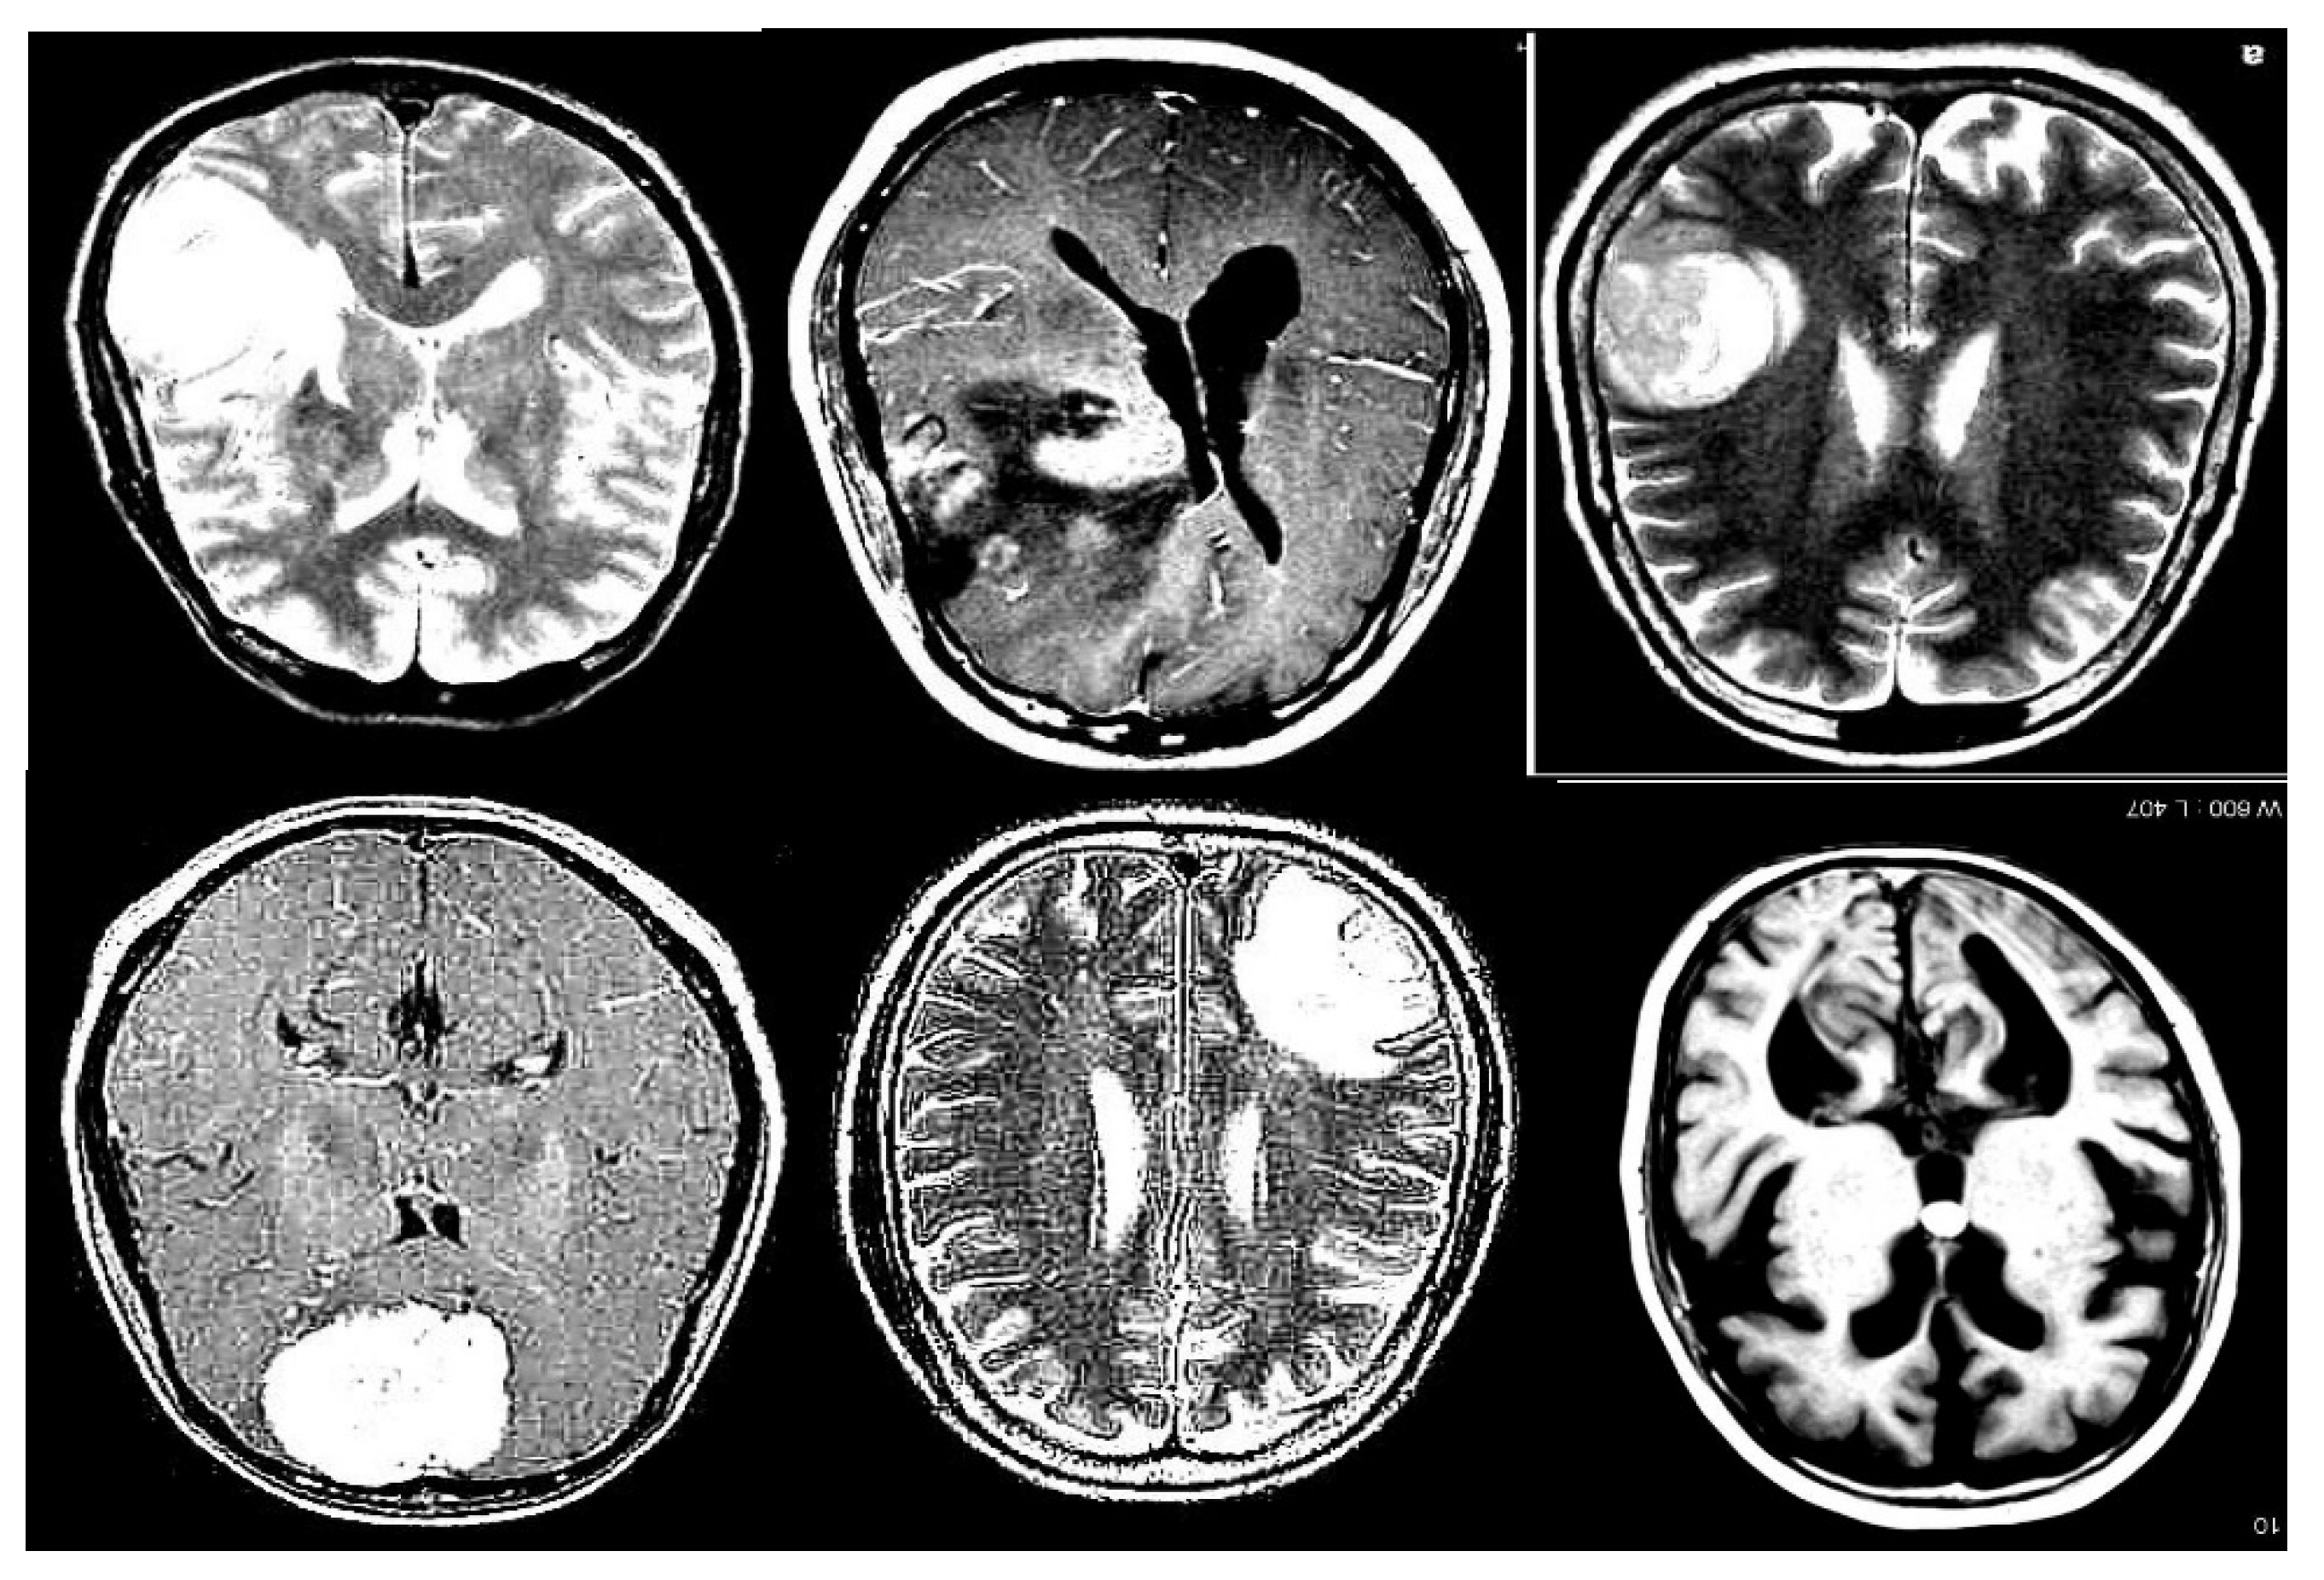

The Roboflow platform was used to access a specific tumor detection project, utilizing the provided API key for authentication. Once authenticated, the project was accessed, and the corresponding dataset version was downloaded. The dataset consists of 3,580 images at 640x640 resolution, divided into 3,130 training images, 299 validation images, and 150 test images, as illustrated in Figure 2. This dataset is labeled according to the tumor classes present in medical images and is formatted for compatibility with YOLOv11.

Figure 2. Set de imágenes para el entrenamiento.